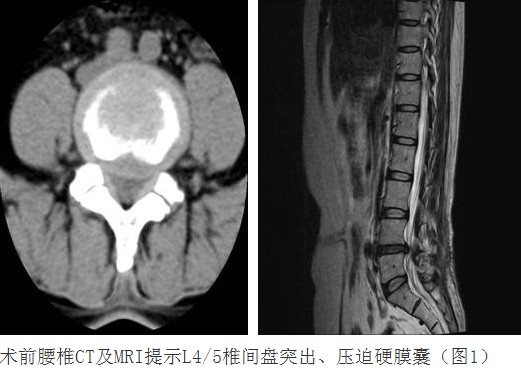

病例匯報(bào)1老年女性患者,因“反復(fù)腰腿痛10年、加重伴左下肢麻痛2月”之主訴入院,術(shù)前左下肢肌力3+級(jí),淺感覺減退。術(shù)后腰腿疼緩解,肌力及感覺恢復(fù)正常。(1、圖2)

術(shù)后腰椎X線提示單側(cè)釘棒系統(tǒng)固定穩(wěn)妥,椎間隙高度恢復(fù)正常,融合良好。(圖2